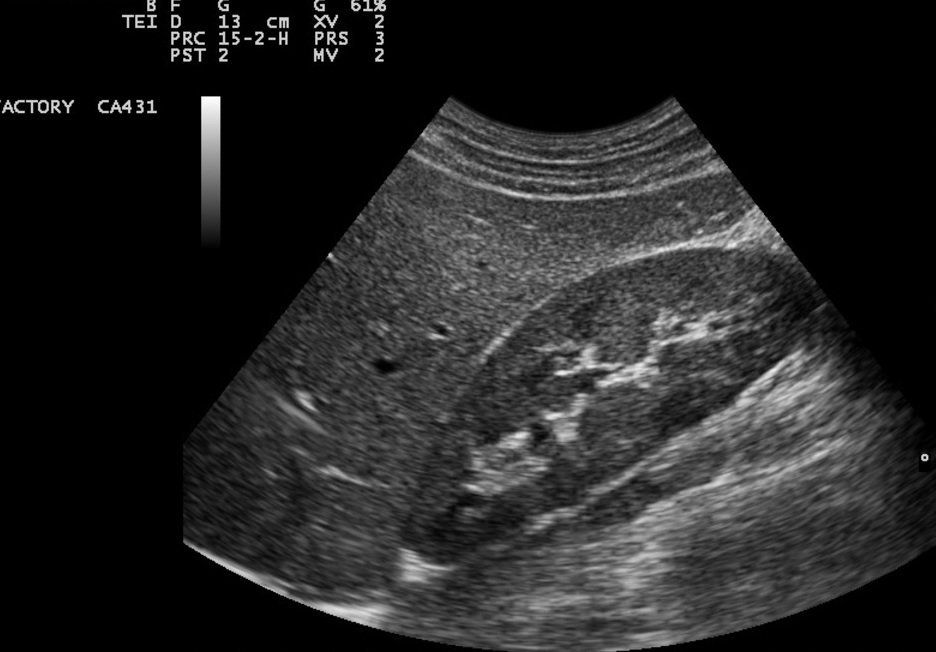

Kidney, Ureter and Bladder Scan

A detailed investigation to look at the size, character and shape of kidneys, Ureter, full bladder and empty bladder.